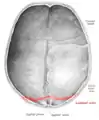

![]() Lambdoid suture (labeled at bottom right) | |

The lambdoid suture (or lambdoidal suture) is a dense, fibrous connective tissue joint on the posterior aspect of the skull that connects the parietal bones with the occipital bone. It is continuous with the occipitomastoid suture.

The lambdoid suture is between the paired parietal bones and the occipital bone of the skull. It runs from the asterion on each side.

The lambdoid suture is named due to its uppercase lambda-like shape.